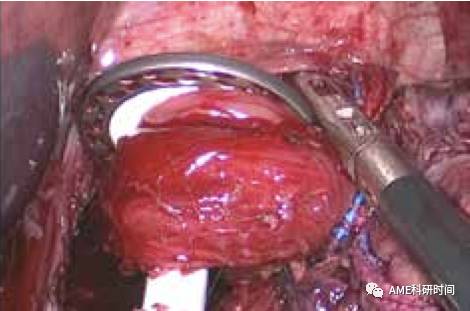

3空肠空肠侧侧吻合:用45 cm丝线测量,距食管空肠吻合处远端45 cm处与近端空肠用直线切割闭合器行侧侧吻合,缝合关闭共同开口及小肠系膜孔(如图39-40)。

图39 空肠侧侧吻合

图40 缝合共同开口

注:既往行食管空肠Roux-en-Y吻合术往往需要将小肠系膜血管弓离断,并离断数支二级血管弓,自从观看减肥外科手术后,发现消化道重建并不需要过度游离Roux-en-Y肠袢。不过游离的好处,在于行空肠侧侧吻合时,可以在腹腔外进行,更加省时及可靠(如图41-42)。